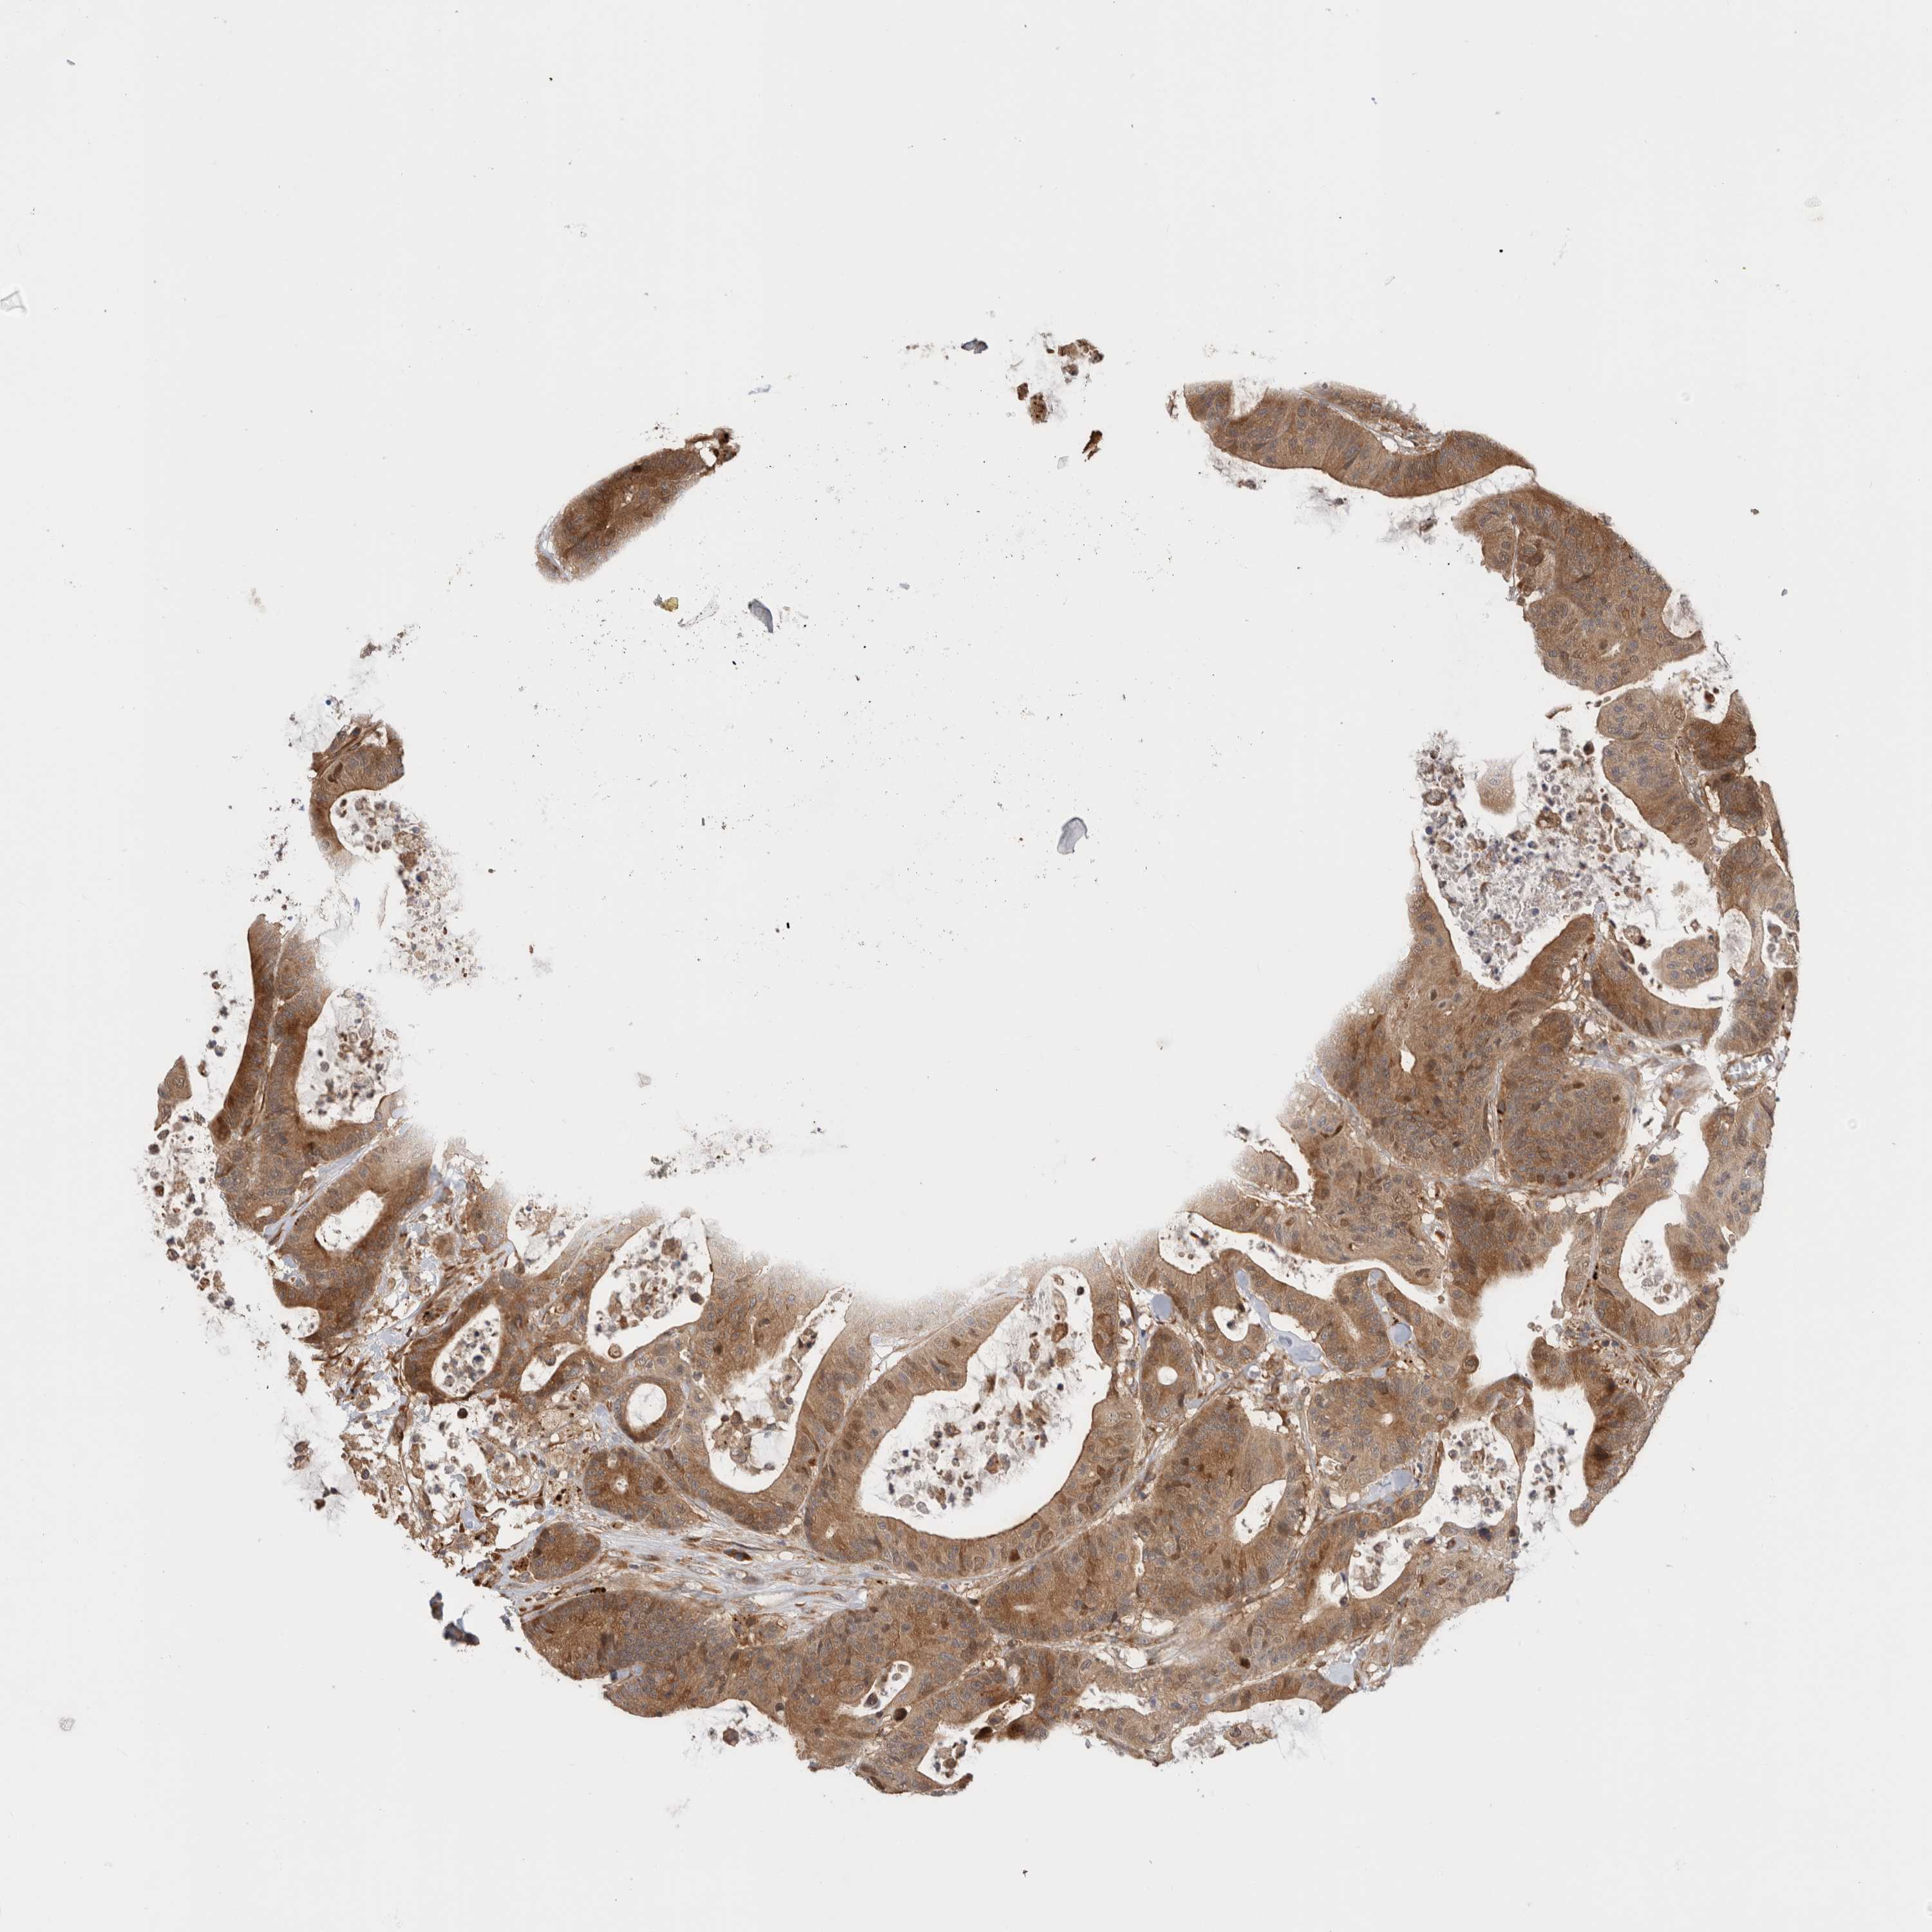

CANCER COLORECTAL CANCER Show tissue menu

Colorectal cancer

Human cancer

Colon adenocarcinoma